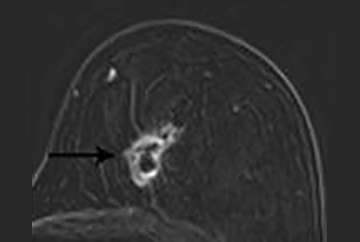

A new enhancing mass (Figure 5), especially those with irregular or spiculated margins, are highly suspicious (BI-RADS 4 or 5).